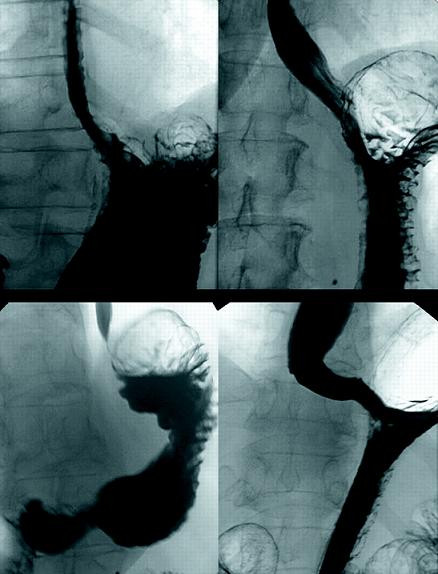

GI là một chuỗi các cơ quan nội tạng của cơ thể sống, bao gồm cổ họng, hoặc hầu họng, thực quản và dạ dày. Đường tiêu hoá (GI) thường khá mềm, với một vài khúc cong có thể thay đổi nếu thật sự thư giãn.

Khi nghệ sĩ trình bày màn nuốt kiếm, sự thư giãn hoàn toàn của đường thượng tiêu hoá (GI) là yêu cầu tuyệt đối phải tuân thủ.

Đầu tiên, người nuốt kiếm ngửa đầu ra sau, kéo dài cổ sao cho miệng và thực quản thẳng hàng với nhau và họng cũng được duỗi ra.

Bước tiếp theo, đẩy lưỡi ra khỏi đường đi của kiếm và thư giãn họng tối đa.

Bước thứ 3: Sắp xếp sao cho cây kiếm song song với đường tiêu hoá (GI) và đẩy cây kiếm đi qua miệng, cổ họng, cơ vòng thực quản trên và vào thực quản. Dưới sự kích thích, tuyến nước bọt sẽ tiết ra dịch bôi trơn cây kiếm. Một số người biểu diễn sử dụng dầu thực vật hoặc sữa ong chúa làm tác nhân bôi trơn.

Bước thứ 4: Trên đường đi xuống dạ dày, thanh kiếm sẽ làm thẳng những khúc cong của thực quản.